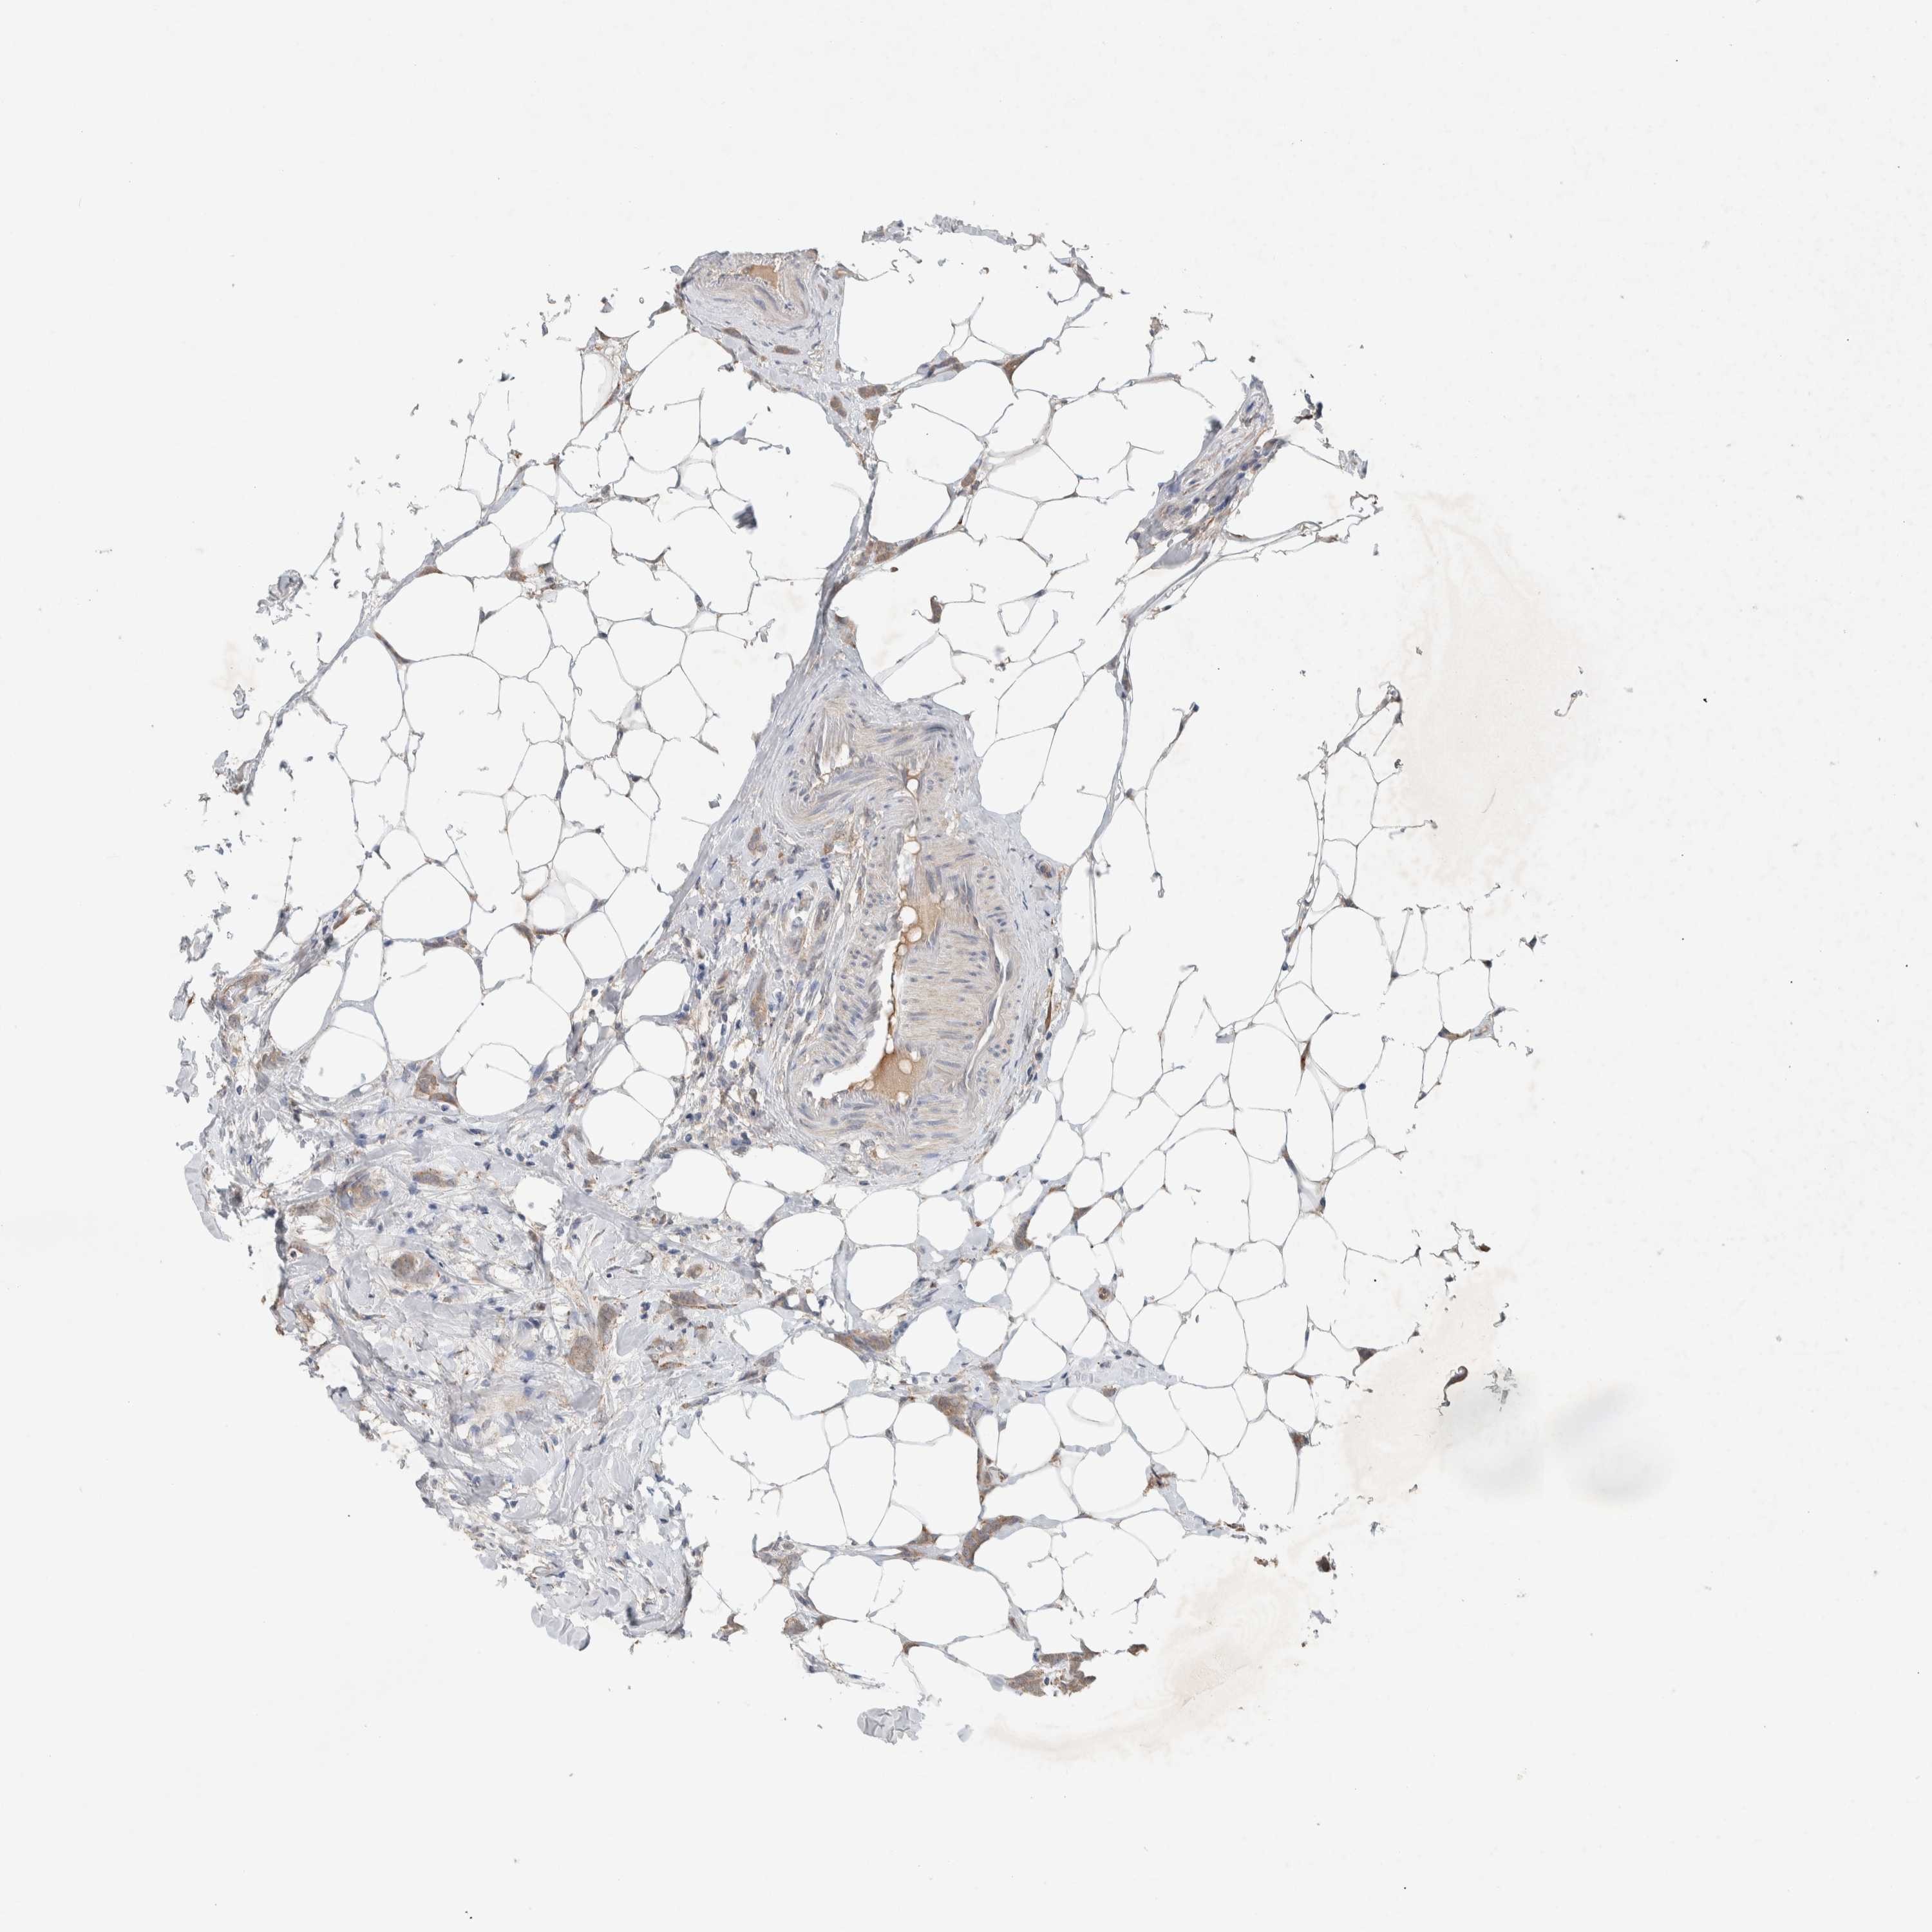

BRCA TCGA BRCA VALIDATION PROTEIN EXPRESSION